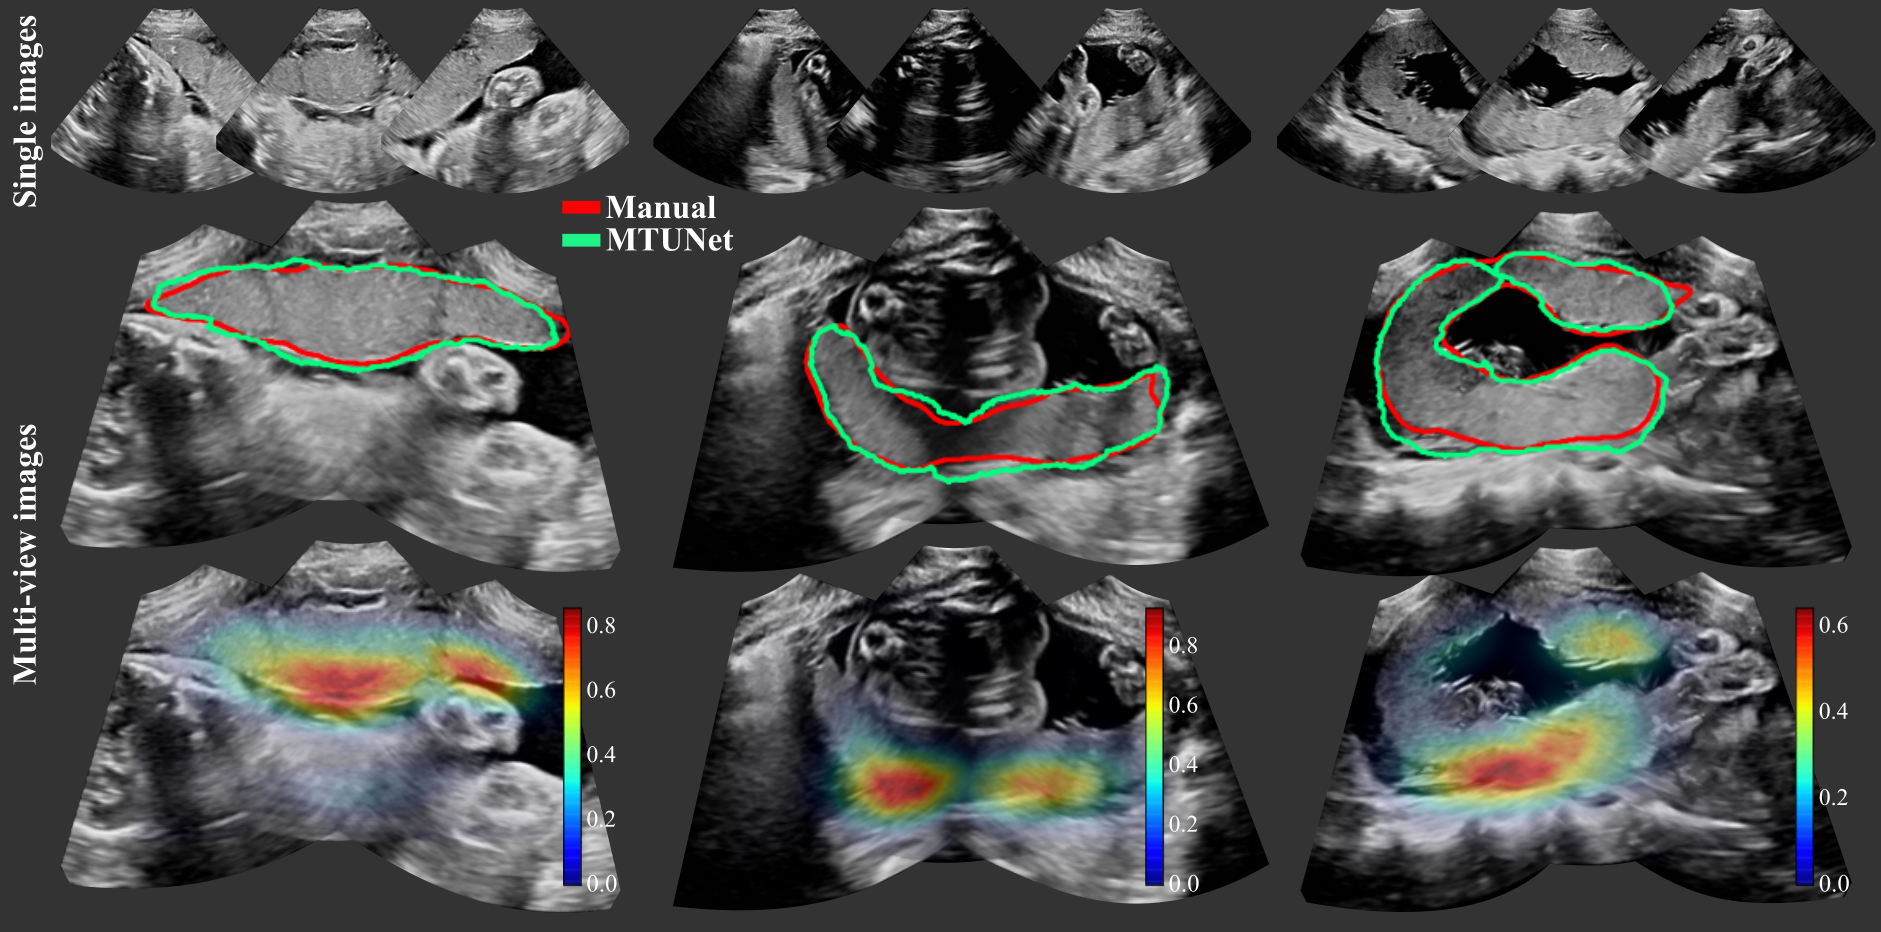

When the spatial transformation between multiple images is known, e.g., by using a multi-probe system as described in Sec. 2 for image acquisition, the segmentations in individual images can be combined to obtain the segmentation in the multi-view image. The multi-view segmentation performance is reported in Table 3 and representative results are shown in Fig. 5.

We observe that, in agreement with the results on single views, pre-training significantly improves the performance on OoD data, especially TMTUnet, showing a strong effect size. We would like to emphasize the performance increase on OoD data of TMTUnet trained on set P. Compared to the second best model, TUNet, the ASD is improved by 58.1% (11.81 mm to 4.95 mm) and the RHD by 34.8% (29.22 mm to 19.04 mm).

Interestingly, the performance on OoD data is in general higher on the multi-view data than on single view data. We emphasize here again that the segmentations are obtained from the single view image models and then fused for a multi-view image segmentation. The manual annotations are created on the fused images directly. We surmise that the increased performance measured on multi-view OoD data might be due to the artifact reduction in multi-view US.

For the majority of the performance measures, the multi-task model MTUNet performs best on both anterior and posterior placentas on the representative training set AP. This is statistically significant for the measures Dice, IoU and ASD with a moderate effect size.

Examplary multi-view images are shown in Fig. 5 with corresponding placenta segmentations with MTUNet and combined attention maps. The placenta is better visualized in the multi-view images with reduced image artifacts and an extended FoV. The multi-task model MTUNet provides an accurate segmentation and the combined attention maps localize well the placenta. Further examples of multi-view images with corresponding segmentations can be found in Fig. 12 in the appendix.